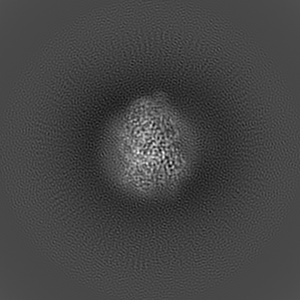

Human Amylin1 Receptor in complex with Gs and cagrilintide

Single-particle2.2 Å

Sample: Human Amylin1 Receptor in complex with Gs and cagrilintide

Structural and dynamic features of cagrilintide binding to calcitonin and amylin receptors.